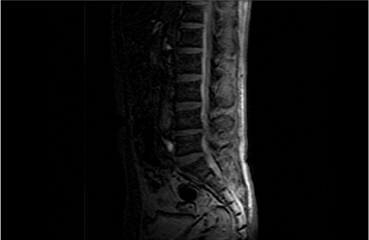

척추체와 척추관 사이에서 척추의 정렬 및 안정화, 운동성을 유지하기 위해

존재하는 구조물을

후종인대라고 합니다. 다양한 원인에 의해 후종인대가 뼈처럼

단단하게 굳어지는 골화를 일으켜 척추관을 압박함으로써 신경장애가 나타나는

질환을 후종인대 골화증이라고 합니다.

목 부분인 경추에서 주로 발생하며,

경우에 따라 가슴 쪽 흉추에서도 드물게 발생합니다.